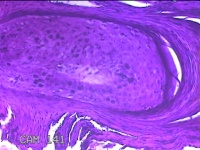

额部肿物

性别

女

年龄

32岁

临床诊断

寻常疣

一般病史

额部起疹1年,不痒。

标本名称

大体所见

灰白暗红色肿物0.7x0.5x0.2cm一个,表面光滑,切开肿物呈实性,切面灰白粉红色,质软。